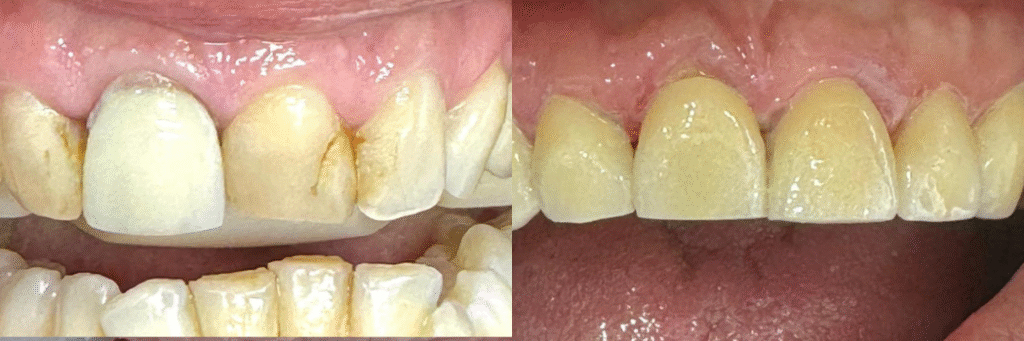

Carilla en diente desvitalizado

A small river named Duden flows by their place and supplies it with the necessary regelialia. It is a paradisematic country, in which roasted parts of sentences fly into your mouth. Even the all-powerful Pointing has no control about the blind texts it is an almost orthographic life

One day however a small line of blind text by the name of Lorem Ipsum decided to leave for the far World of Grammar. The Big Oxmox advised her not to do so, because